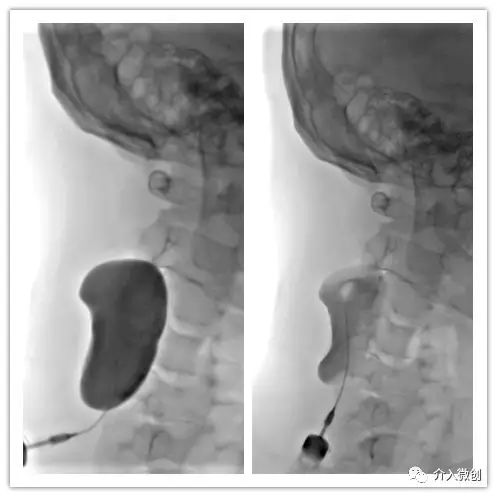

成人颈部淋巴管畸形

DSA引导下经皮穿刺囊腔,抽吸囊液,囊腔内注射硬化剂硬化治疗。